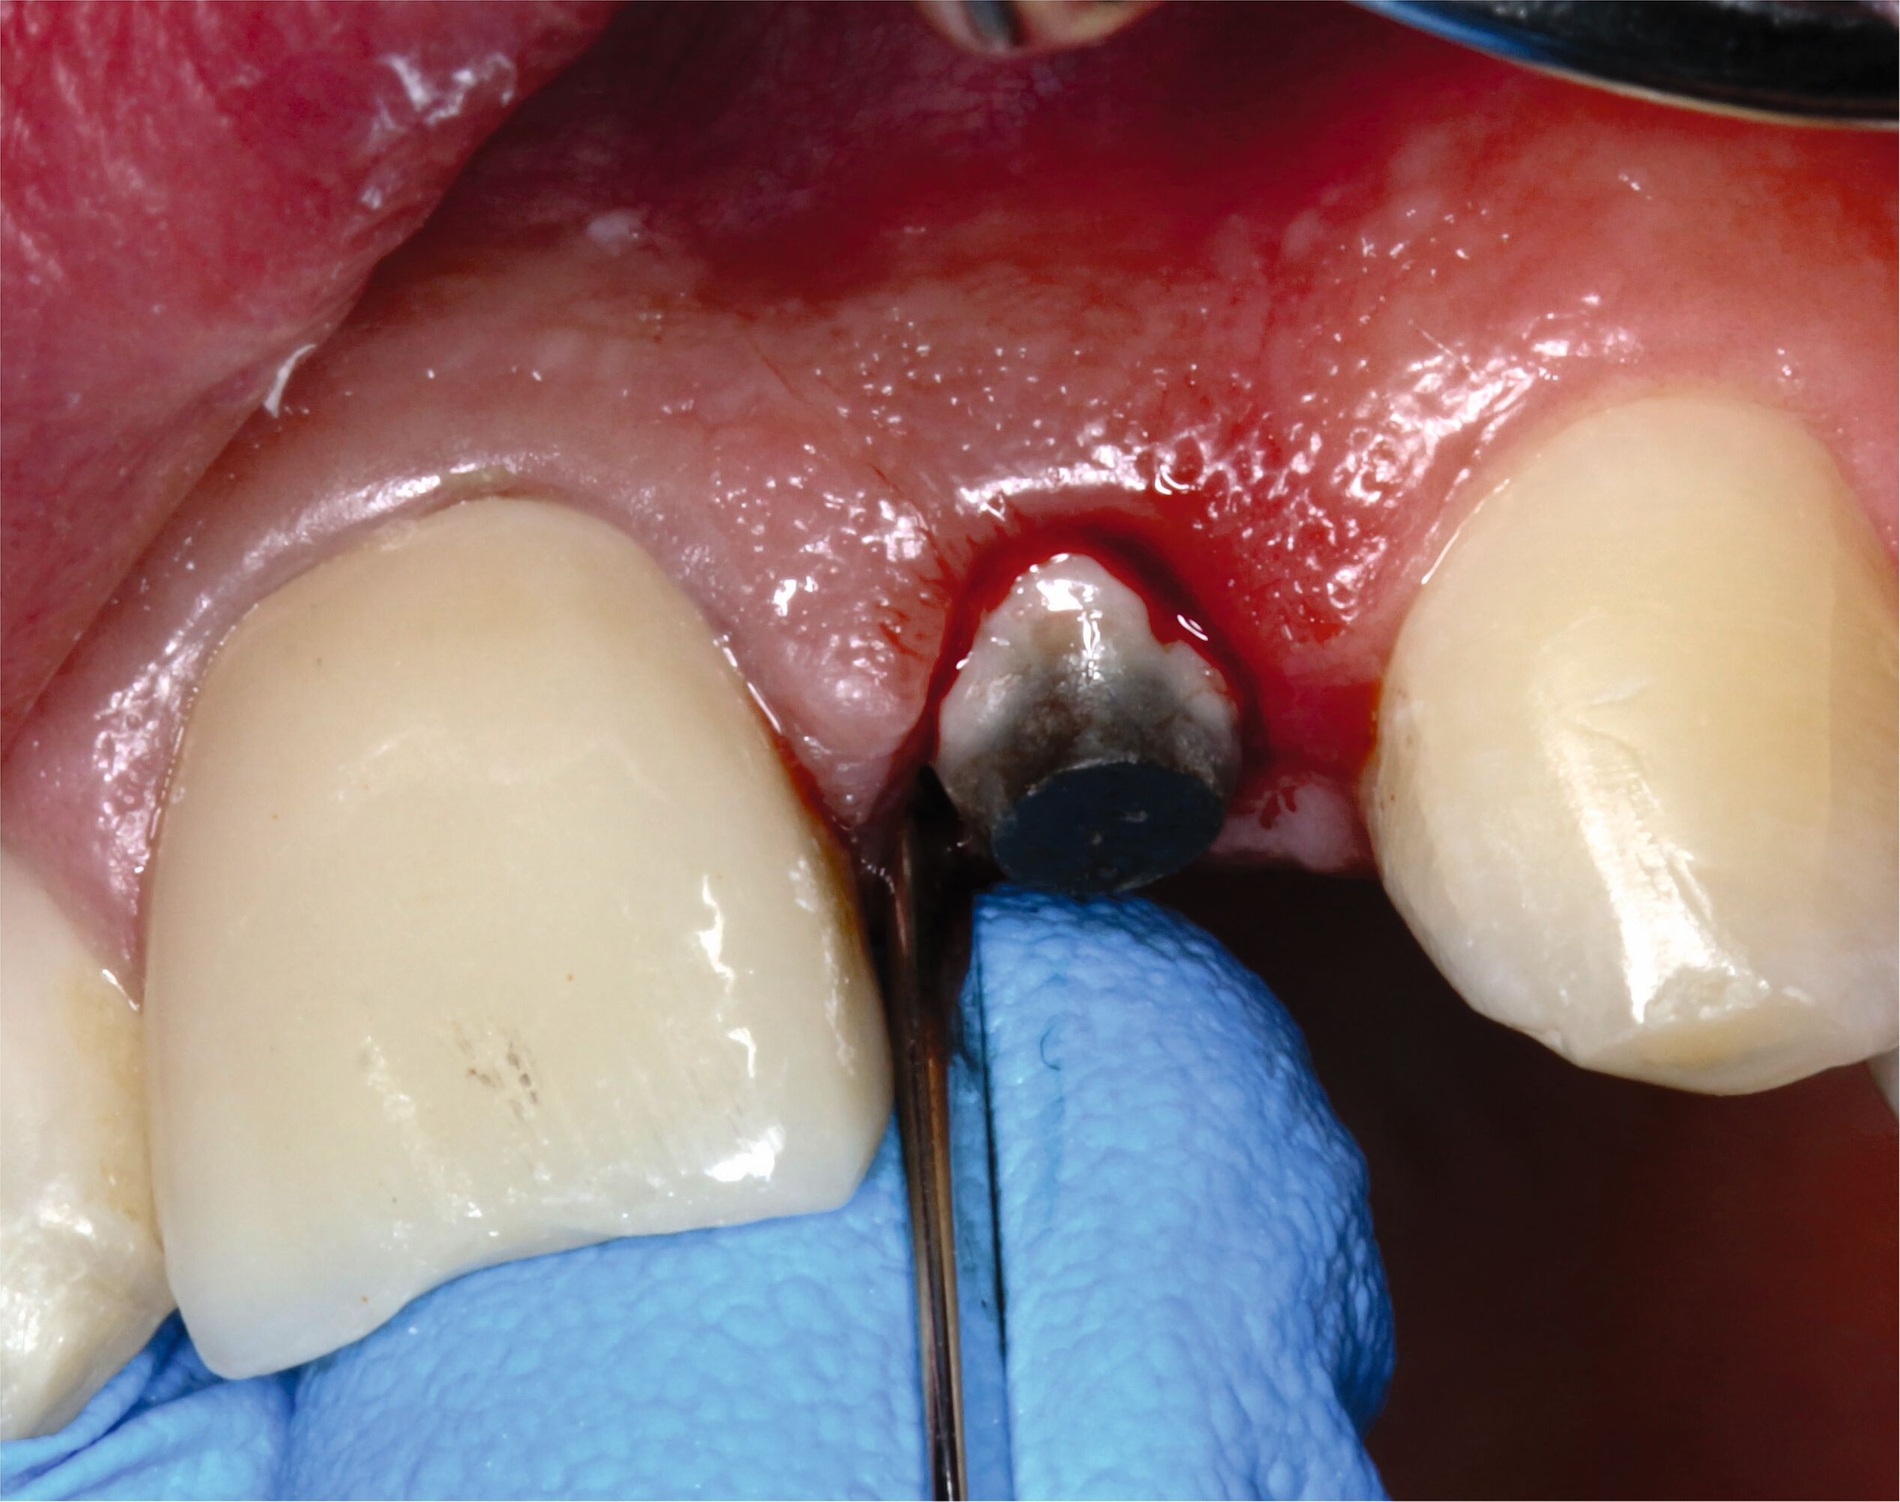

Anhand der von uns durchgeführten Einzelzahnaufnahme konnte die alio loco gestellte Erstdiagnose korrigiert werden: Wurzelfraktur des Zahnes 22 mit Kommunikation zur Mundhöhle (Abbildung 19). Der Patient favorisierte nach Diagnosesicherung zunächst Zahnersatz an 22 durch ein Sofortimplantat, weshalb eine DVT-Aufnahme zur weiteren Planung angefertigt wurde (Abbildung 20). In der Aufnahme zeigte sich jedoch, dass keine suffiziente vestibuläre Knochenlamelle vorhanden und somit der Erfolg eines Sofortimplantats nicht sicher vorhersagbar war. Nach umfassender Aufklärung entschied sich der Patient für den Zahnerhalt und eine Extrusion mit Magneten (Abbildungen 21 bis 24).

Nachdem eine Wurzelkanalbehandlung durchgeführt worden war, wurde der Magnet adhäsiv befestigt und die Zahnwurzel bis circa 4 mm über das Knochenniveau bewegt. Hierfür waren wochenweise Recalltermine notwendig, um den Magneten in der Schiene umzupositionieren und durch suprakrestale Fibrotomie die parodontalen Fasern zu lösen (Abbildung 22 und 23).

Als die Wurzel des Zahnes 22 ausreichend extrudiert war, wurde ein adhäsiver Stift-Stumpf-Aufbau inseriert (Abbildungen 24 und 25). Die Krone an Zahn 21 wurde entfernt, da diese durch das Trauma inzisal beschädigt worden war und der Patient eine Neuanfertigung wünschte.